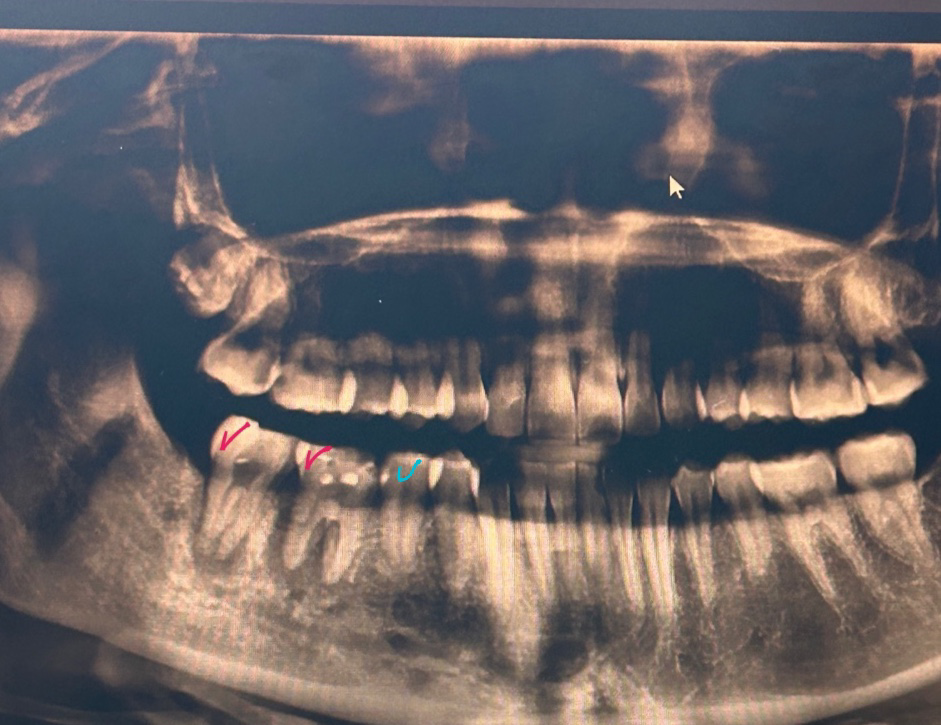

빨간색으로 표시한 쪽이 염증이 심해서 임플란트나 신경치료를 해야한다고 안내를 받았는데 신경치료중 안되겠다 싶어서 오늘 발치하러갔는데 하늘색 부분도 상태가 안좋다하고 위에 잇몸도 염증이 심해서 오늘은 치석제거랑 약처방받고 다음 주에 발치하자고 하시던데 지금 빨간색 부분말고 하늘색체크 표시랑 다른 치아도 발치가능성이 있나요?